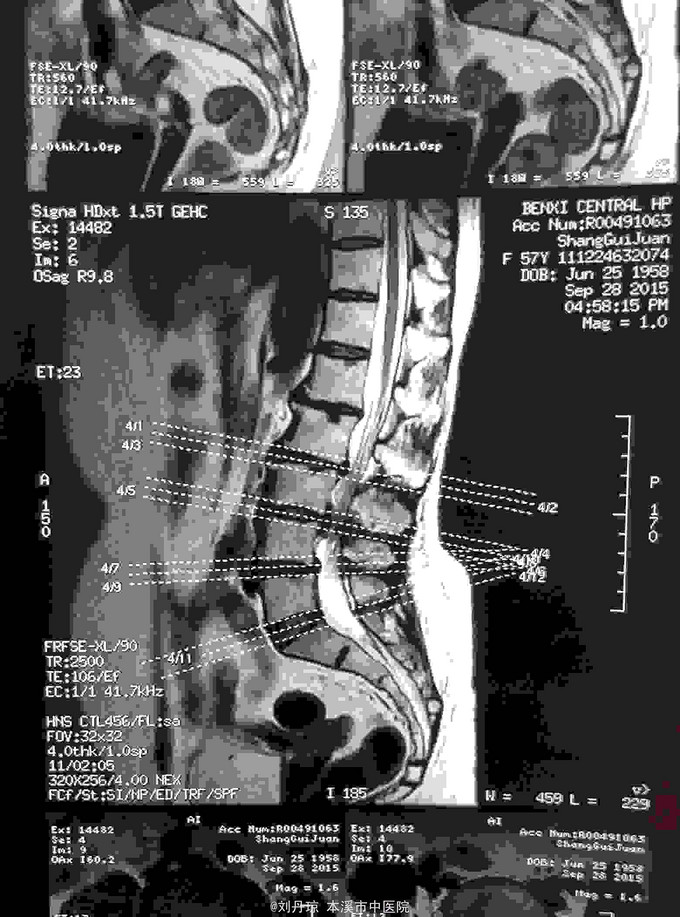

腰部疼痛伴右下肢放射痛麻木感半年,加重2月。患者半年前劳累后感到腰部疼痛伴右下肢放射痛麻木感,近2月病情加重来诊。

查体:L1—S1棘突右旁压痛阳性。直腿抬高实验左70度,右40度。 直腿抬高加强实验左侧阴性,右侧阳性。腰椎功能障碍。 辅查:CT: L1—S1椎间盘突出。

诊断:腰椎间盘突出症 治疗:针灸、雷火灸、中药熏药治疗、小针刀治疗、骶管注射治疗、营养神经药物治疗、脱水药物治疗,当归地黄饮加味。